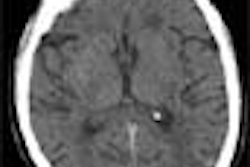

The study looked at 75 asymptomatic patients routinely referred for CAC scoring. Two sets of prospectively gated studies (diastolic phase) were acquired on the same day for each patient using the Siemens scanner with an adaptive array design. Continuous images were acquired with detector collimation of 3 x 2.5 mm in 2.5-mm slice sequential scanning mode, with partial volume reconstruction performed on a Siemens 3-D Virtuoso workstation. The entire 120-mm z-axis sequence coverage, from the carina to the base of the heart, took approximately 18 seconds at 20-40 mAs. Temporal resolution was 250 ms with partial volume reconstruction.

The total calcium scores ranged from 0 to 2,498 HU, and the average inter-observer difference was 20 HU with a range of 0 to 288.

Moreover, the mean difference between the first and second scan was 25 HU, with a range from 0 to 473. Most of the large differences between observers were concentrated in differentiating aortic wall, left main artery calcifications and beam hardening artifact, and not the detection of calcification itself.